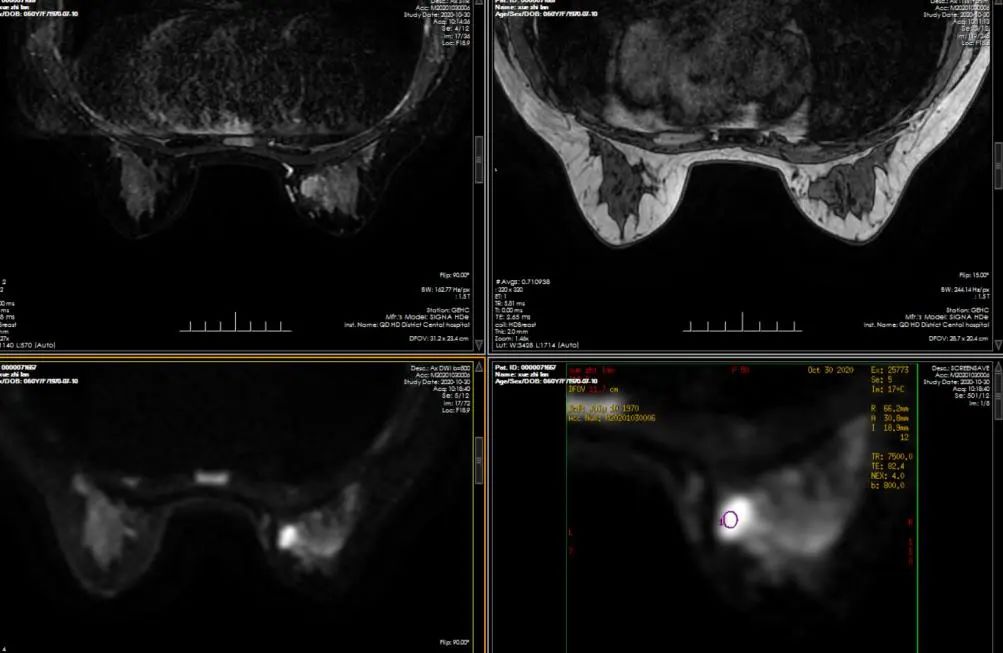

乳腺磁共振成像(MRI)

乳腺MRI具有多参数、多序列及功能成像的优势。可评估肿瘤的形态学、血流动力学及组织功能代谢等改变。MRI应用动态增强多参数以及扩散加权成像中获得的ADC值有助于乳腺良恶性病变的鉴别诊断,实现了形态学+血流动力学+分子生物学,其敏感性94%-100%,特异性80%-97%。目前MRI因其具有的独特优势已成为乳腺癌新辅助治疗(NAT)疗效评估的常规影像学检查方法,其作用明显优于乳腺X线摄影及超声检查。诊断符合率高达97%,能发现X线、超声无法发现的早期和微小乳腺癌,能检出的最小乳腺癌为1mm;对有乳腺癌家族史、携带乳腺癌相关基因的妇女,应较早接受MRI检查;检查尽量在月经周期第2周进行。